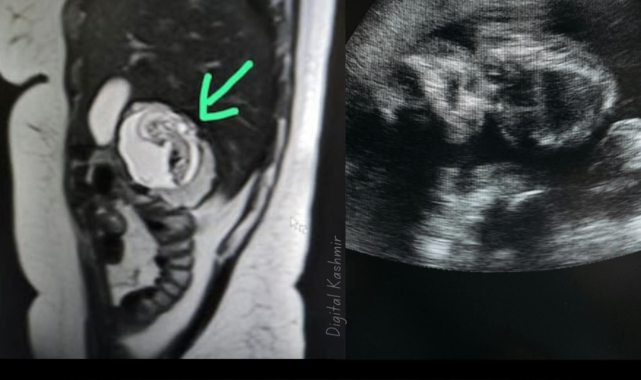

Şiddetli karın ağrısı şikâyetiyle hastaneye başvuran kadına yapılan görüntüleme sırasında doktorlar, hamileliğin rahim yerine karaciğerde geliştiğini fark etti. Tıp dünyasında son derece nadir görülen bu duruma intrahepatik ektopik gebelik adı veriliyor.Erken tanı ve başarılı cerrahi müdahale sayesinde kadının hayatı kurtarıldı.Uzmanlar bu vakayla birlikte, anormal gebeliklerde erken tıbbi müdahalenin hayati önem taşıdığına dikkat çekiyor.Bu olay, dünya genelinde yalnızca birkaç kez kayda geçmiş vakalar arasında yer alıyor ve tıp literatüründe Hindistan’dan bildirilen ilk vaka olarak kabul ediliyor.

Uttar Pradesh’te doktorlar, bir kadının karaciğerinde gelişen 12 haftalık fetüs tespit ederek Hindistan’da kaydedilen ilk intrahepatik ektopik gebelik vakasını ortaya çıkardı.